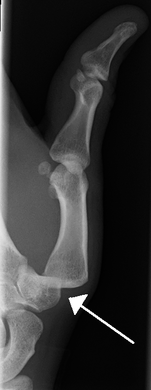

Dislocation of the left index finger

Radiograph of right fifth phalanx bone dislocation- Radiograph of left index finger dislocation